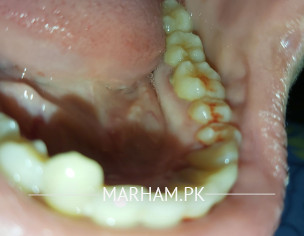

Hello reader !! from past months I am having gum bleeding, but sometimes it is in excessive amount. I have started taking vitamin C , my gums were fine but yesterday again I have conquered this issue. Bleeding is more when I pressed gum. Google is showing some super weird stuffs about this problem. Can you tell me what's the issue.

as per the image. it seems Gums infection.plz visit a dentist and get teeth cleaning and polish done.

close up

You have gingivitis and need sub gingival (Deep) scaling

you need deep gums cleaning (scaling) your problem will b solved dont worry

your gums are injected and require scaling for their treatment.